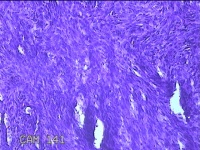

右侧前臂结节

性别

女

年龄

38岁

临床诊断

皮下结节

一般病史

发现右侧前臂结节1年余。

标本名称

大体所见

灰白粉红色带皮肤样组织0.8x0.7x0.3cm一块,表面带梭形皮肤0.8x0.7cm,皮下见结节0.8x0.5x0.3cm一个,切开结节呈实性,切面灰白粉红色,质软。